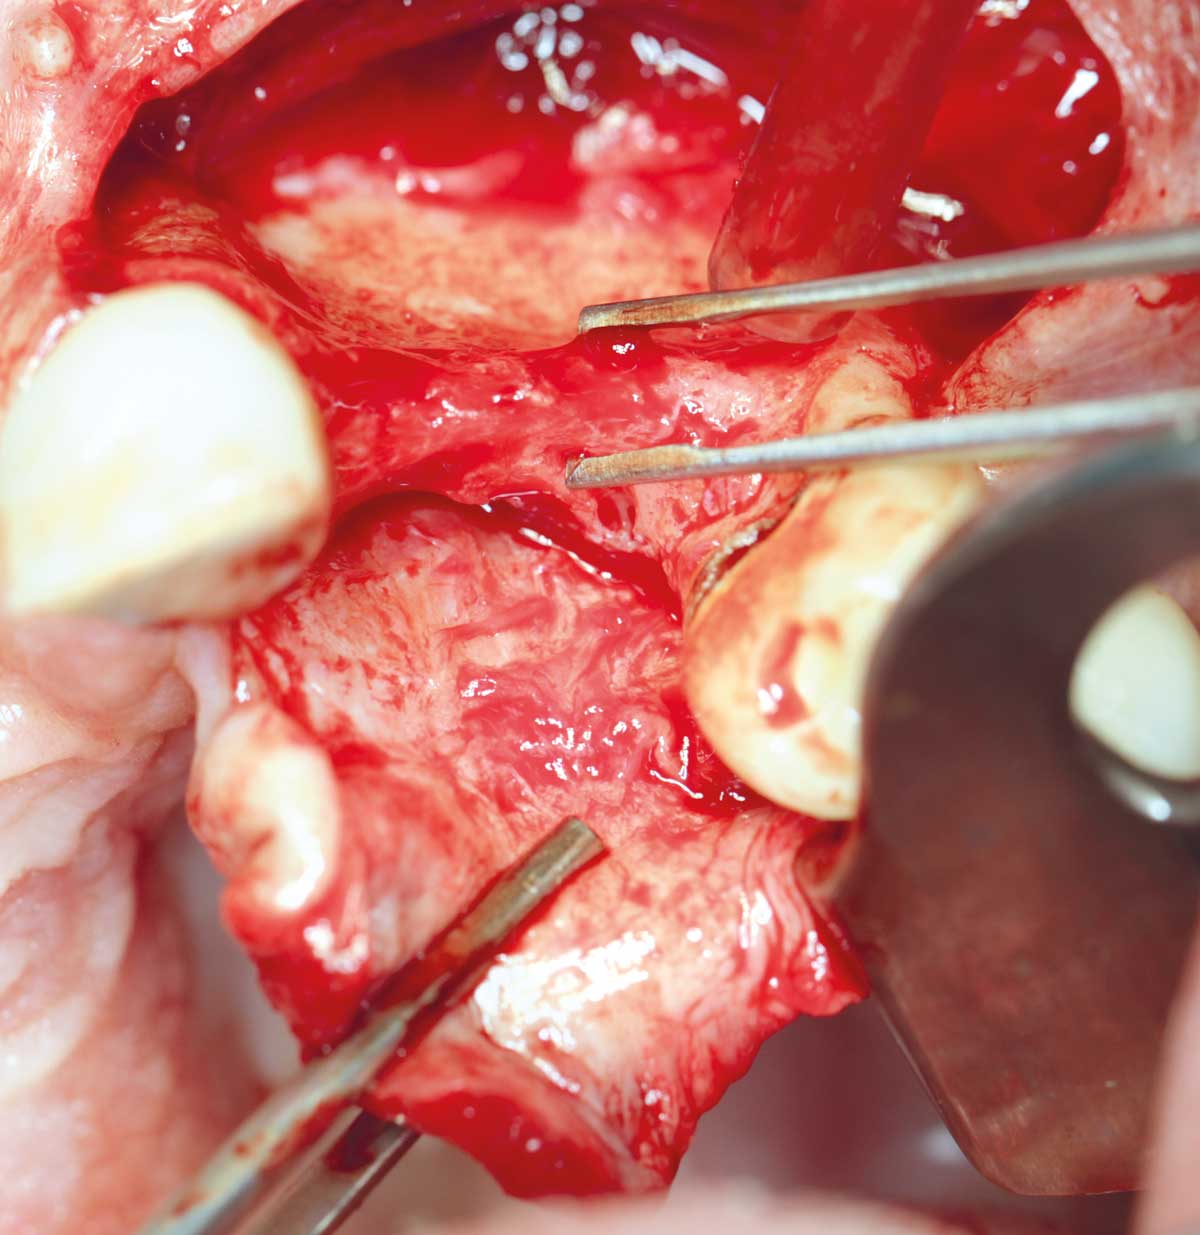

Preparation of a single tooth defect with severely resorbed vestibular wall